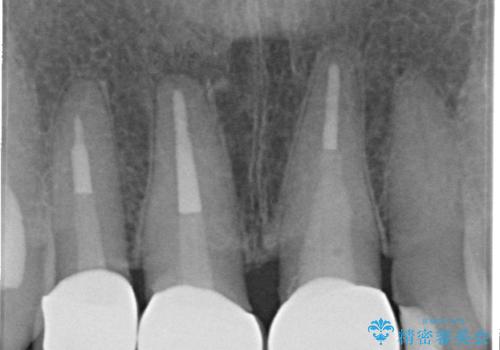

結婚式に合わせて根管治療からのやりかえを短期集中治療で計4回で終える計画を立てます。

- 40万円(仮歯・ファイバーコア・ジルコニアクラウン×3)費用は治療当時の料金となります

セラミック治療は外から見えるのはクラウンの色味・形態、歯肉の状態のみですが、X線撮影において現れるクラウンと歯牙の適合や、ファイバーコアの精度・根管充填の密度に、より長い予後を達成するための要素が含まれると考えます。